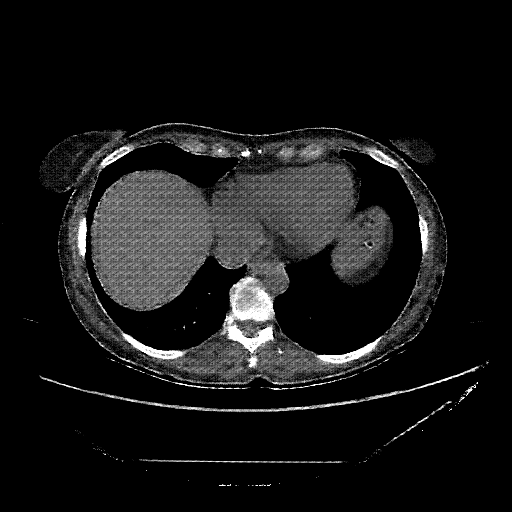

Image Grid

4Γ—3 grid: Rows show different image types (Original NATIVE, Reconstructed NATIVE, Original VENOUS, Generated VENOUS), Columns show windowing techniques (No Window, Lung Window, Mediastinum Window)

Generated VENOUS CT scan (A→B translation)

Lung window (WL -600, WW 1500 β†’ Low βˆ’1350, High +150)

Mediastinum window (WL 40, WW 400 β†’ Low βˆ’160, High +240)